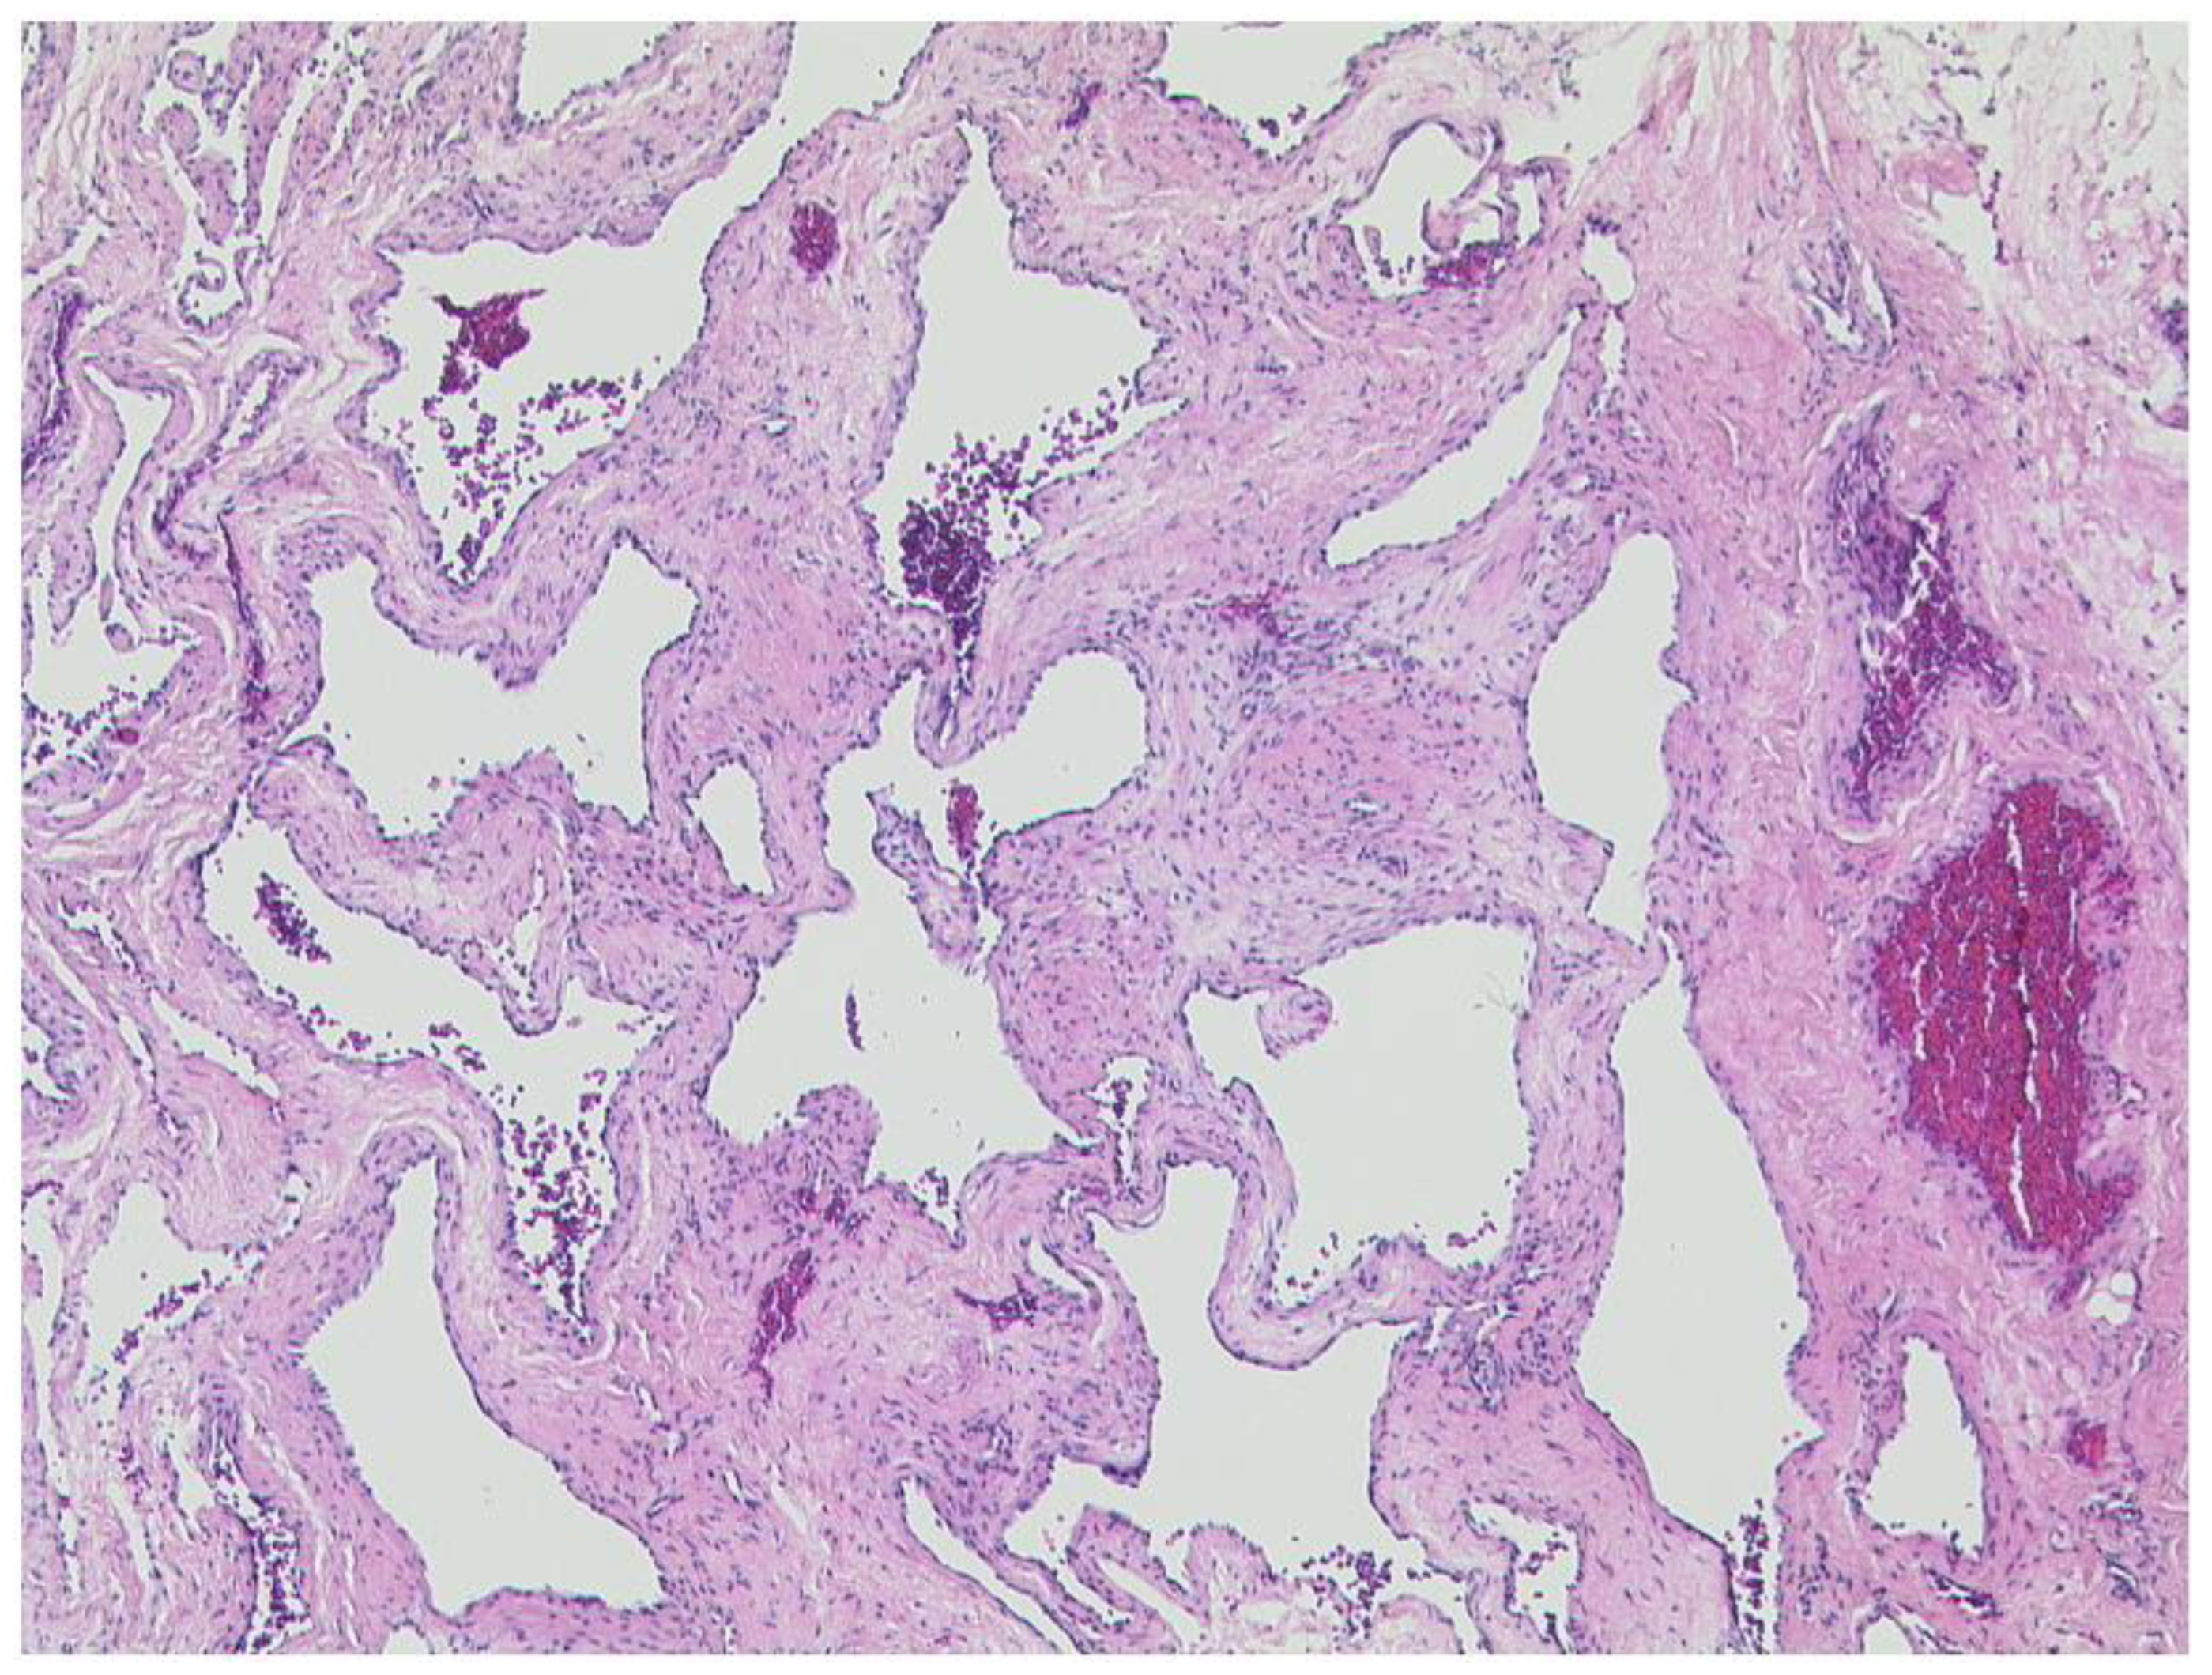

3.2.2. Cavernous Hemangioma